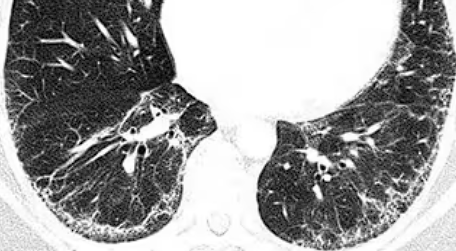

- CT 소견: 간유리 음영, 망상 음영, 견인성 기관지 확장증 등 미세한 변화가 관찰됩니다.

ILA(간질성 폐 이상)는 특별한 증상이 없는 사람의 흉부 CT에서 '우연히' 발견되는 소견을 말합니다. 폐의 간질(폐포와 혈관 사이의 조직)에 미세한 변화가 관찰되지만, 아직 특정 '질환'으로 진단하기에는 충분하지 않은 상태를 의미합니다. 마치 피부에 작은 점이 생겼지만, 아직은 암이라고 진단하지 않고 경과를 지켜보는 것과 비슷합니다.